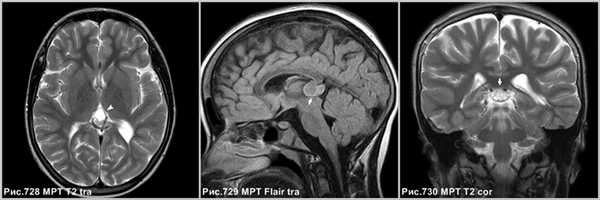

Объёмное образование шишковидной железы, представленное мягкотканным образованием с наличием капсулы (стрелки на рис.729, 730). Пинеоцитома может иметь кисты (головка стрелки на рис.728).

На КТ и МРТ солидные компоненты интенсивно накапливают контраст [34,43,49,53,130].

Интенсивное контрастирование солидных участков пинеоцитомы (стрелки на рис.731-733).

Дифференциальный диагноз

Герминома

Герминома - злокачественная, чаще солидная опухоль с петрификатом в центре, в то время как пинеоцитома обызвествляется по периферии. Герминома метастазирует и инфильтрирует таламусы.

Пинеобластома

Пинеобластома - первично злокачественная опухоль (как медуллобластома, ретинобластома или эпендимобластома, прежде входила в состав ПНЭО). Опухоль плохо отграничена, имеет инвазивный характер роста. Возникает в возрасте до 20 лет. Содержит кисты и некрозы, обычно крупная на момент первого исследования и осложненная гидроцефалией. Всегда имеются метастазы.

Киста шишковидной железы

Постконтрастное Т1 демонстрирует накопление агента в солидном участке опухоли (стрелки на рис.734). В центре герминомы определяется петрификат (стрелка на рис.735) и отсутствующее обызвествление по периферии. Накопление контраста в стенке кисты шишковидной железы (головка стрелки на рис.736).